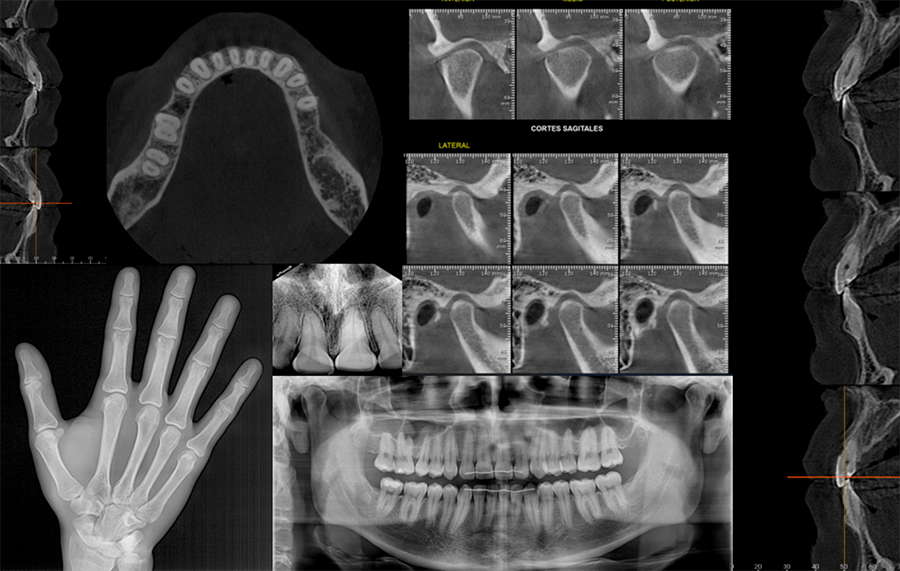

· Radiografía Panorámica

· Radiografía de mano

· Radiografía Periapical

· Tomografía Maxilar

· Tomografía de mandíbula

· ATM MIC

· Tomografía de zonas maxilares